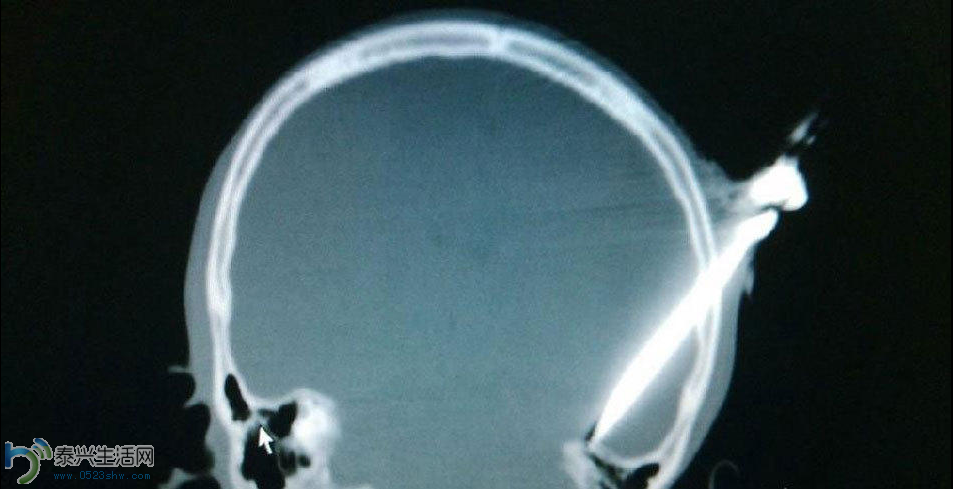

图为1月1日,伤者头顶着匕首被紧急送往东华医院抢救。插入伤者头顶的匕首长约8公分,其中有6.5公分完全刺进了颅内。

据东华医院神经外科主任沙龙金称,一把匕首直插头部,脸上身上全部是血,这是新年第一天17岁的少年小杨被紧急送院的场景。“当时伤者基本上是处在一个人事不省的状态。插入伤者头顶的匕首长约8公分,其中有6.5公分完全刺进了颅内,贯穿了整个脑组织,从顶骨一直插到颅底,并且也插进去了部分岩骨。”沙龙金说,伤口位置很深,比较凶险,伤者随时会有生命危险。图为匕首贯穿了整个脑组织。图片由医院提供